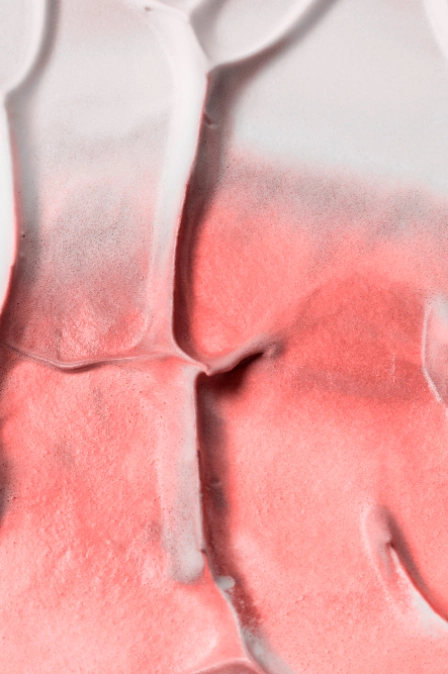

- эритематозная — через 6-12 часов развиваются отграниченная гиперемия (переполнение плазмой артерий), отек, эритема (покраснение) в месте заражения;

- эритематозная — красный валик по периферии, который очерчивает отек, раздражение эпителия, краевая болезненность, повышение местной температуры;